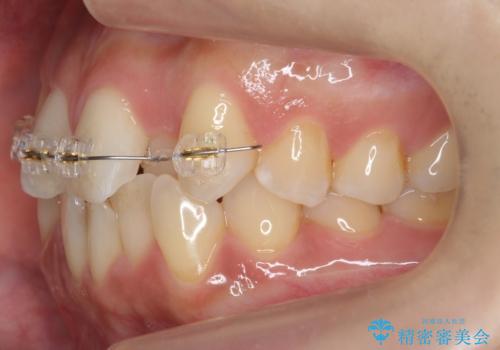

- 矯正装置

- インビザライン

上はワイヤー部分矯正、下はインビザライン(マウスピース)で部分矯正を行いました。

下の前歯を内側に入れる為、一本抜歯しています。